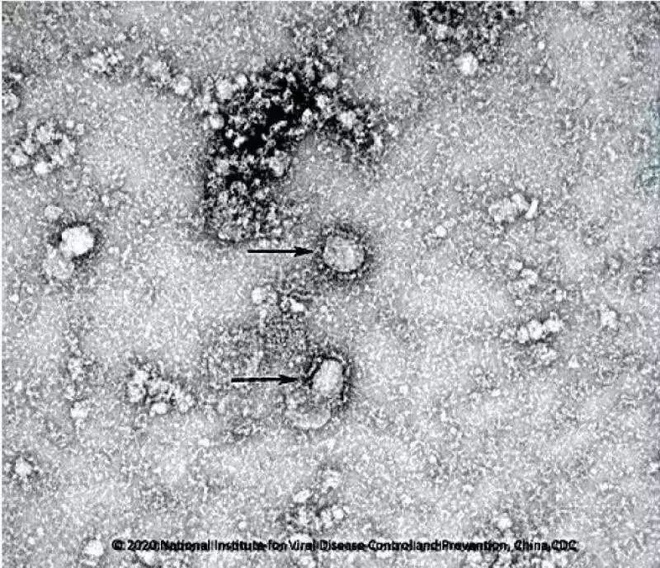

Hình ảnh chủng virus corona dưới kính hiển vi điện tử. Ảnh: Trung tâm Kiểm soát và Phòng ngừa dịch bệnh Trung Quốc.